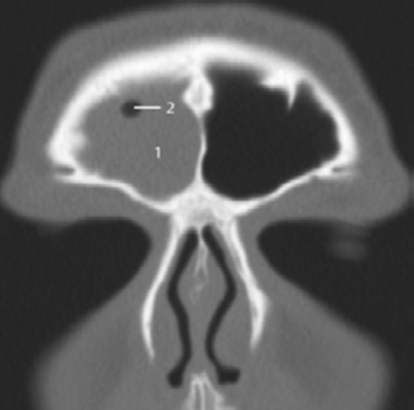

L’échographie abdominale réalisée objectivait une vésicule à paroi fine siège de plusieurs mini-calculs (Figures 1, 2).

La tomodensitométrie abdominale avec opacification confirmait cette cholécystite avec un foie hétérogène, siège de multiples microlésions arrondies hypodenses, rehaussées légèrement après injection de produit de contraste (Figures 3, 4).